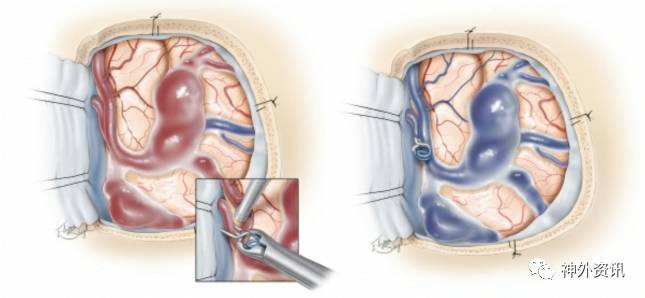

图3. 图示为左侧额骨后方开颅,夹闭向上矢状窦中部引流的单根窦旁dAVF。动脉化的皮层静脉上可见静脉扩张,这种现象在该类型的dAVFs中非常常见,具有较高的出血风险(左图)。在动脉化静脉与静脉窦连接处放置血管夹,导致瘘口闭塞(左图,插图),可见曲张静脉转为暗蓝色(右图)。术中荧光造影确认在扩张或曲张静脉内已呈乏血流状态。无需切除曲张静脉。